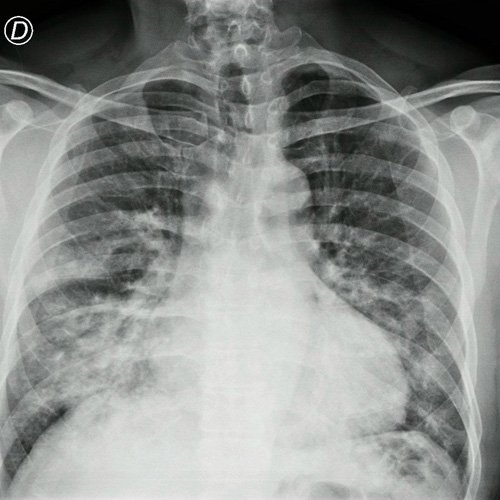

- Radiografía de tórax frente/perfil (Dia 0): rotada, bien inspirada, índice cardiotorácico impresiona conservado , se observa infiltrado parenquimatoso a nivel medio basal de campo pulmonar derecho e izquierdo, senos costofrénicos impresionan libres..

Radiografía de tórax frente y perfil

Radiografía de tórax frente y perfil